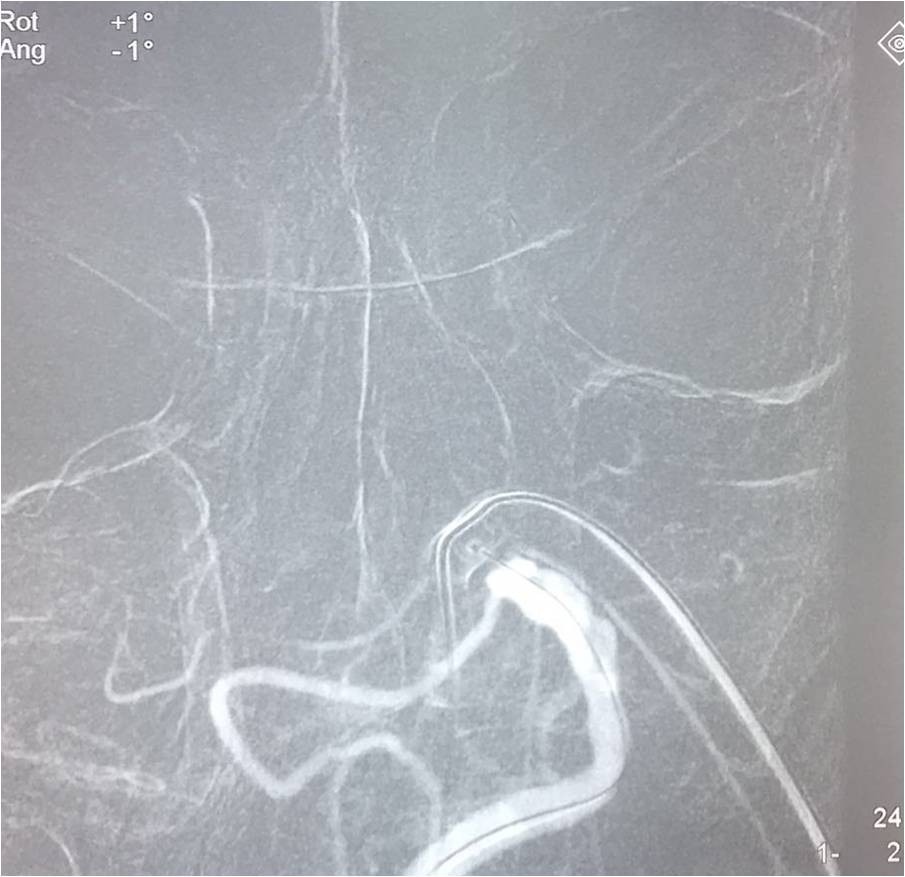

▼复查造影。

治疗效果、预后及随访情况:患者入院后严格按照《2015急性缺血性卒中血管内治疗中国指南》给予诊断治疗。患者术前NIHSS评分≥30分,术后第一天NIHSS评分19分,病情未进一步加重,肢体肌力恢复到3级,神志较前好转,病情稳定,进一步康复后,可恢复生活自理。